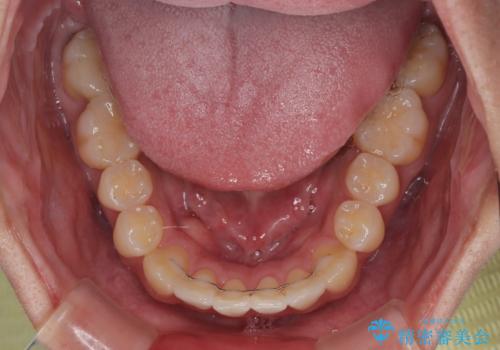

前歯のデコボコをささっと治す 短期間でのインビザライン矯正治療

- 前歯の反対咬合などを気にして来院された患者様です。

ワイヤー矯正、マウスピース矯正どちらでも対応可能であったので、ご本人の希望によりインビザラインにて矯正治療を行うこととしました。

毎日の装着時間をしっかりと守ってくださり、1年強の短期間で、あっという間に治療を終えることができました。